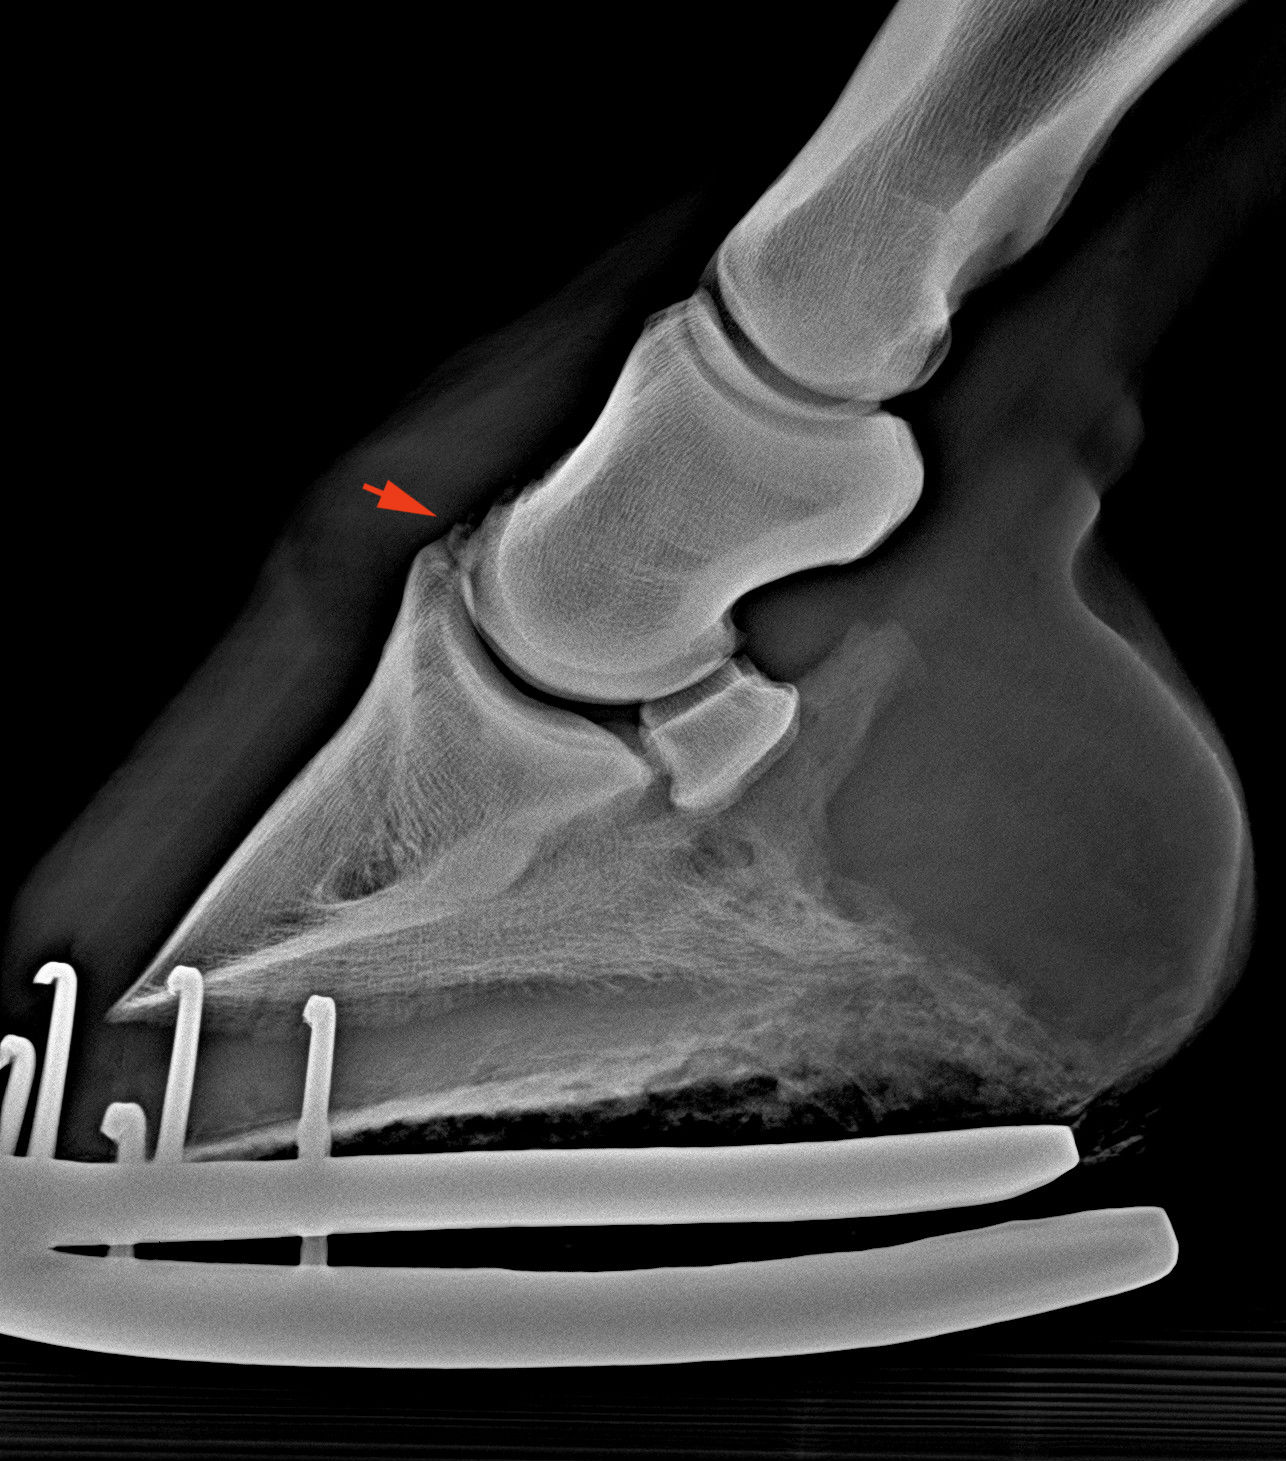

Apró letört csontdarab, „chip” a patacsontról (piros nyíl)

Ugyanaz az elváltozás, csak „nagyban”